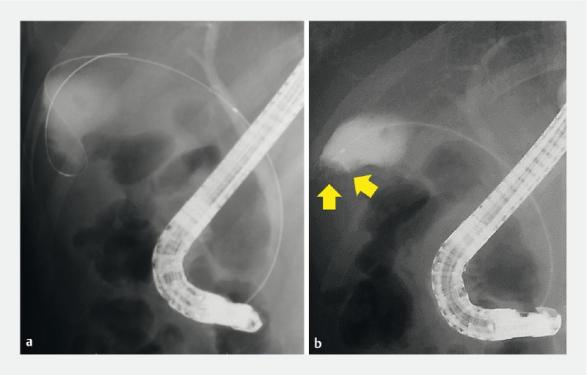

Fig. 2 Imaging studies of gallbladder cancer showing a tumor lesion (yellow circle) at the gallbladder fundus. a Contrast-enhanced computed tomography. b Magnetic resonance imaging.

图2. 对胆囊癌的影像学研究显示,胆囊底有一个肿瘤病变(黄色圆圈)。a. 对比增强计算机断层扫描。b. 磁共振成像。

A 79-year-old man presented to our hospital with a gallbladder tumor diagnosed using abdominal ultrasonography (AUS). AUS, contrast-enhanced computed tomography, and magnetic resonance imaging showed a protruded lesion at the gallbladder fundus (Fig. 1, Fig. 2). Endoscopic retrograde cholangiography (ERC) was performed, and cholecystography revealed a contrast agent defect at the gallbladder fundus (Fig. 3).

患者,男,79岁,入院后通过腹部超声检查(AUS)诊断出患有胆囊肿瘤。AUS、对比增强计算机断层扫描和磁共振成像显示,胆囊底部有一个突出病变(图1、图2)。进行了经内镜逆行性胆管造影(ERC),且胆囊造影显示,胆囊底部造影剂充盈缺损(图3)。